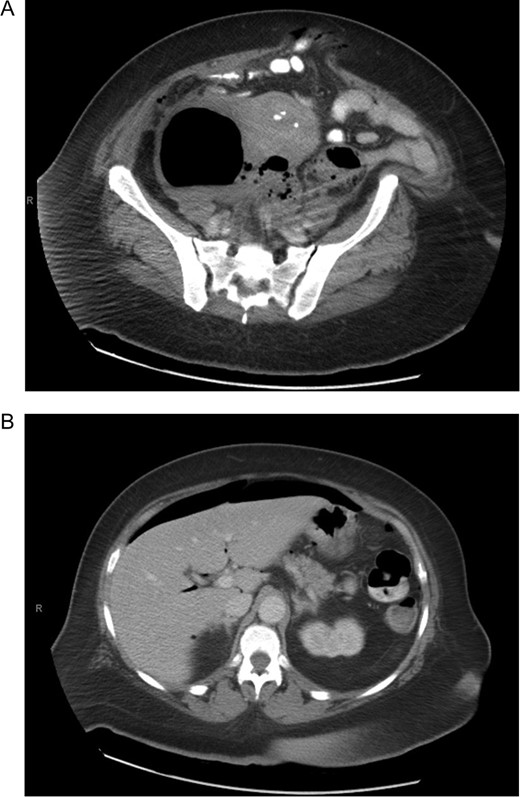

A 63-year-old African American female presented with complaints of abdominal pain located more in the right lower quadrant and multiple episodes of vomiting for the past 4 days. She had a history significant for ventral hernias and past surgical history of two myomectomies. Physical exam demonstrated right upper and right lower abdominal tenderness and peritoneal signs. Patient had fever and tachycardia. Chest x ray showed free air under the diaphragm (Fig. 1). Computer tomography revealed pneumoperitoneum and alarge gas containing collection in the pelvis measuring 13.6 Ă— 8.8 cm2. This was in close proximity to the sigmoid colon which appeared thickened, and extending to the right adnexal region (Fig. 2A and B). Laboratory results showed white blood cell count 28.7 Ă— 103/ ÎĽL, 93% neutrophils. The patient was taken to the operating room for exploratory laparotomy with the presumptive diagnosis of perforated sigmoid diverticulitis.

(A) Computer tomography showing pelvic collection. (B) Computer tomography showing pneumoperitoneum.